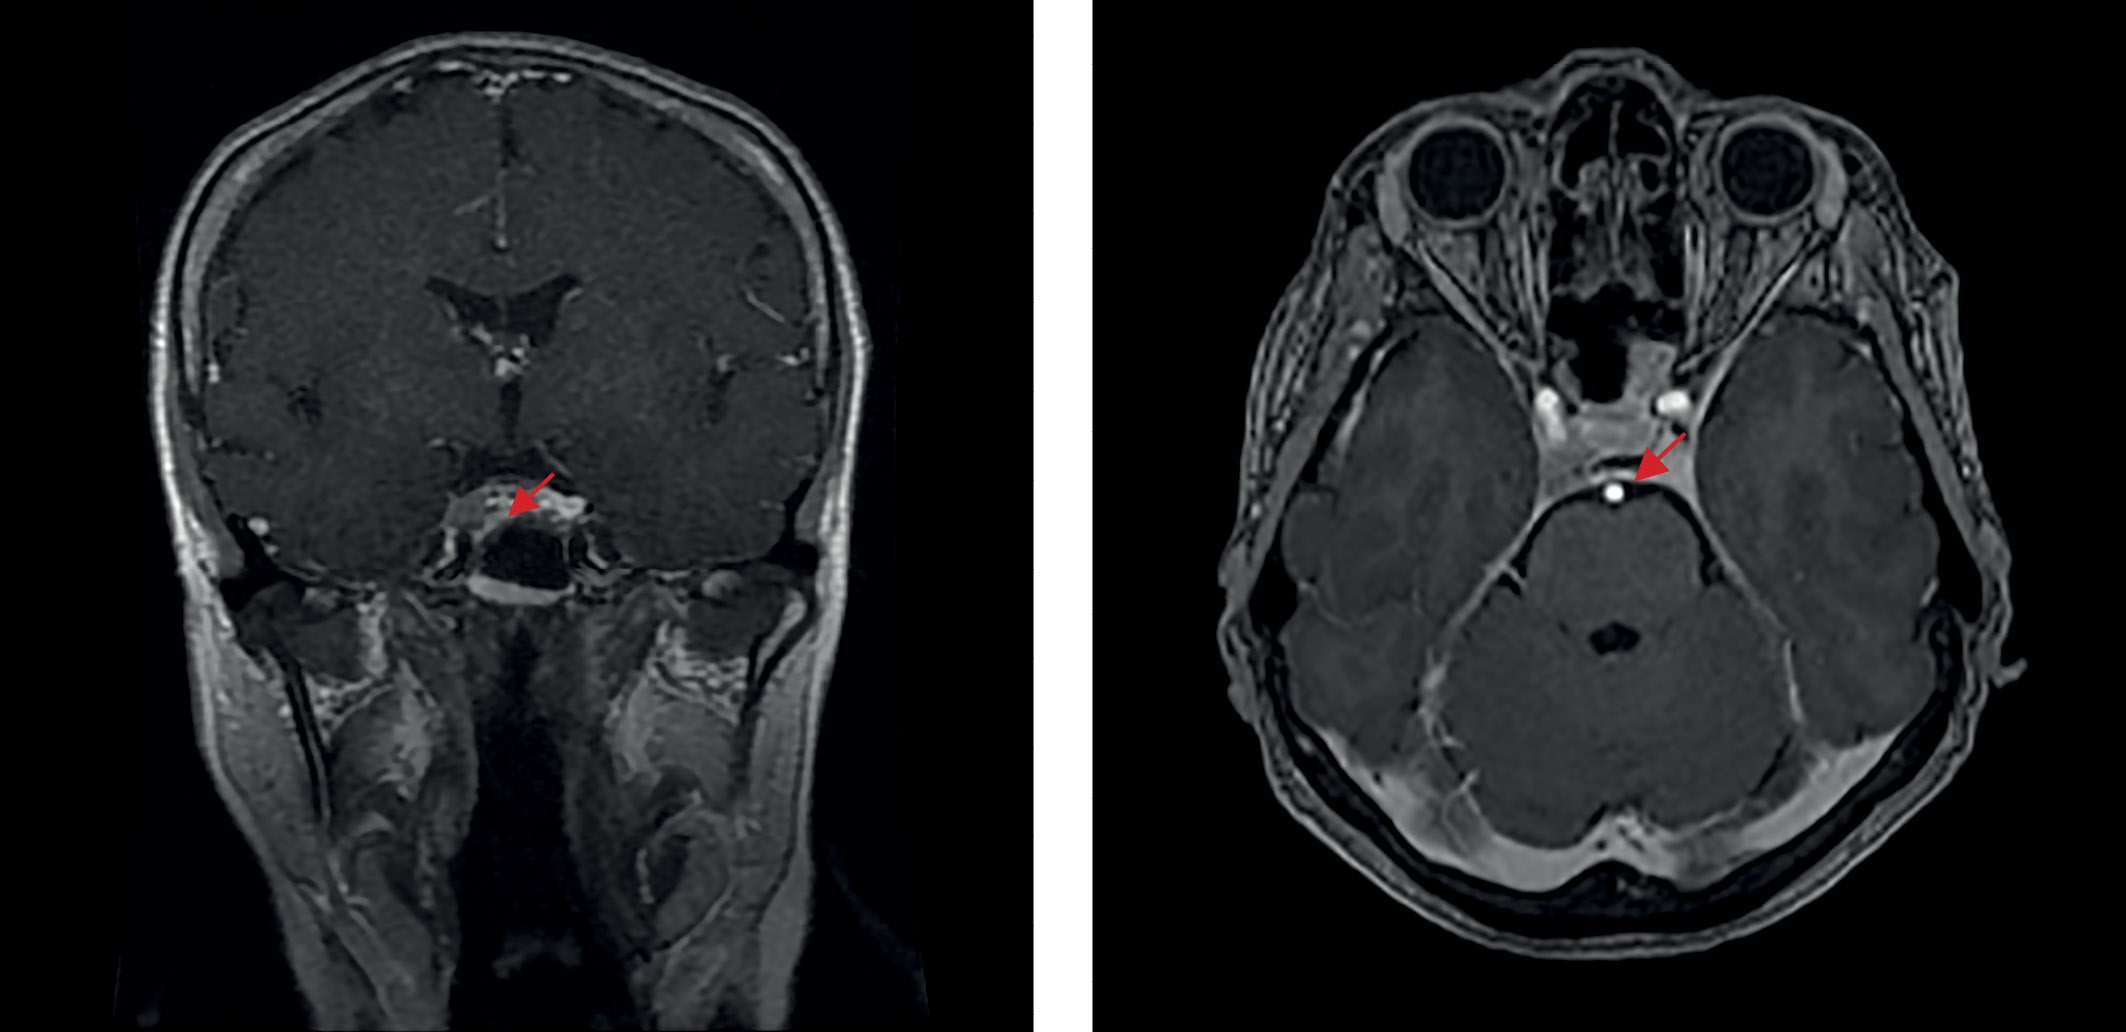

В июле 2021 г. перенесла новую коронавирусную инфекцию (COVID-2019) средней степени тяжести. C августа того же года вновь стала отмечать ухудшение самочувствия в виде повышения аппетита, прибавки массы тела (в течение 3 мес на 7 кг), нарушения сна, общей слабости, онемения конечностей, болей в суставах. По данным лабораторных исследований: декомпенсация по основному заболеванию (кортизол слюны в 23.00 — 27,0 нмоль/л, АКТГ утром — 90 пг/мл, кортизол на фоне малой дексаметазоновой пробы — 596 нмоль/л). При повторной госпитализации в ФГБУ «НМИЦ эндокринологии» Минздрава России в ноябре 2021 г.: кортизол в слюне вечером — 13,46 (0,5–9,65) нмоль/л, кортизол в суточной моче — 398 (100–379) нмоль/сут, ритм АКТГ (утро/вечер) — 63,55/36,65 пг/мл. Проведено МРТ-исследование головного мозга с контрастным усилением (рис. 3), выявлена макроаденома гипофиза размерами 6×9×11 мм с эндо-, латероселлярным распространением вправо, по шкале Knosp-IV (полное окружение кавернозного сегмента внутренней сонной артерии опухолью). При оценке минеральной плотности кости (МПК) методом рентгеновской денситометрии верифицированы остеопения в поясничном отделе позвоночника (-1,3 по Т-критерию) и в левой бедренной кости (-1,0 по Т-критерию), остеопороз дистальной трети левой лучевой кости (-3,1 по Т-критерию). Проведен консилиум совместно с заведующим отделением нейрохирургии, учитывая особенности размеров и характера роста опухоли, отсутствие полной лабораторной ремиссии при наличии ремиссии клинической, было принято решение о динамическом наблюдении и проведении трансназальной транссфеноидальной аденомэктомии на фоне выраженной активности основного заболевания.

Рисунок 3. МРТ головного мозга после трансназальной аденомэктомии, 2021 г.

3. Рисунок 3. МРТ головного мозга после трансназальной аденомэктомии, 2021 г.